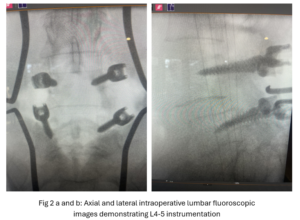

This 50-year-old female with a long history of low back pain and a prior history of multiple lumbar surgeries with instrumentation. She had a L3-5 laminectomy with instrumentation about 7 years prior and now presents with progressive worsening of low back pain. The pain was worse with activity, standing, walking, and prolonged sitting. She had an MRI which showed next segment degeneration at L2-3 with stenosis and the development of a large posteriorly-oriented synovial cyst with thecal sac compression (Fig. 3). The patient failed all means of conservative management including physical therapy and epidurals. We decided to perform an L revision laminectomy to decompress and remove the cyst as well as explore her prior fusion. In this case, again the anterior wall of the sac was completely stuck to the dural membrane. Therefore, we internally decompressed the cyst which was mainly degenerated, necrotic material and removed as much wall of the cyst that could be safely removed. There was some fluid within the cyst. Of note during the dissection of these cysts there is often a release of cyst fluid the patient was well-decompressed. We removed the prior instrumentation and added a new L2-3 construct (Fig. 4). The patient had an uneventful hospital course and was discharged on post op day 2.